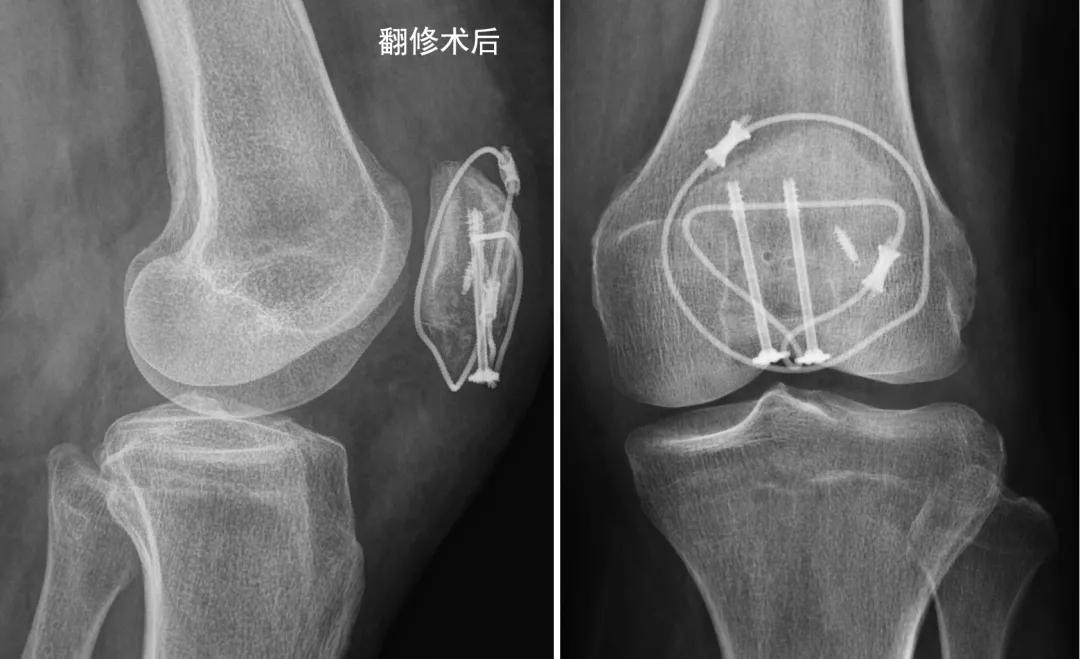

这可怎么办呢?洪女士和家属特别着急,到哪里再次手术呢?通过网络检索,洪女士和家属得知北医三院创伤骨科张志山医生团队采用新型张力带系统治愈了多例类似的髌骨下极骨折。洪女士坐着轮椅来到了张志山医生的门诊。张志山医生仔细检查了洪女士的左膝关节,切口愈合满意,关节活动时疼痛,由于髌骨下极骨折分离,破坏了伸膝装置的连续性,建议再次手术固定髌骨下极骨折。洪女士对第一次手术表达了不满意,认为手术没做好,所以才会造成内固定物松脱。张志山医生给她解释了这个骨折的特殊性,髌骨下极骨折发生于髌骨远端,不累及或者累及较少关节面,其多表现为粉碎性骨折,骨折块相对较小,此外下极是髌腱的起点,应力相对集中,手术固定存在难度。据文献报道,目前有将近10种方法来治疗髌骨下极骨折,说明这个骨折的治疗存在很多问题,各国医生都在想办法解决。洪女士当地医院的医生已经尽最大努力,选择经典的术式来固定她的骨折,术后片子显示骨折复位和内固定物位置都很好,但是由于髌骨下极骨折的特殊性,经典的钢丝克氏针固定技术不能对抗膝关节术后功能练习,所以才出现内固定的失败。张志山医生决定选择新设计的φ3.0mm垫片空心钉组成的新型张力带系统来做翻修手术。术中见钢丝和克氏针已经松脱,部分髌腱撕脱,下极骨折块粉碎。小心复位骨折,拧入带异形垫片的φ3.0mm空心钉(如图)。

异形垫片的小孔穿入钛缆,钛缆穿过髌骨近端的骨洞,在髌前呈8字拧紧,钛缆、异形垫片和空心钉形成一体化的牢固张力带。锚钉修复撕裂的髌腱,钛缆环扎髌骨一圈(如图)。

固定完成后,术中屈伸膝关节,见内固定物很牢固。

洪女士术后恢复顺利,经过艰苦的功能练习,膝关节活动良好,术后2个月骨折愈合,洪女士恢复了正常生活。